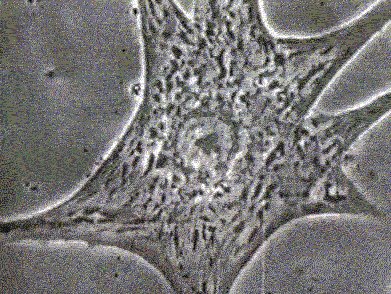

SINAPSIS DEL SISTEMA NERVIOSO CENTRAL

Es la interaccion de neuronas en el sistema nervioso, de ellas depende este sistema. en un terminal axonico aparece una serie de ramas con unas pequeñas regiones dilatadas llamadas «terminales sinapticas» o «botones sinapticos». El boton está separado con el botón de la siguiente neurona por medio de un espacio llamado «hendidura sinaptica». En los botones hay unos espacios llamados «vesiculas sinapticas» que tienen dentro de ellos unas sustancias llamadas «neurotransmisores» la cual se usa para la comunicacion.